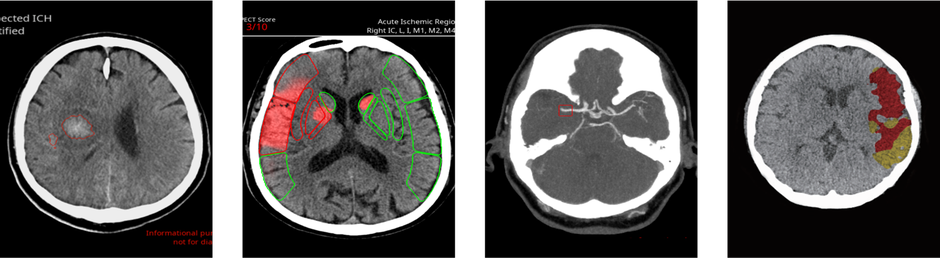

Liječnički tim, koji čine specijalisti Gojko Bogdan i Dorijan Radančević te specijalizanti Kristian Karlović i Robert Prusina, s cijelim timom inženjera i medicinskih sestara osigurava pripravnost tima za mehaničku trombektomiju kod pacijenata s akutnim moždanim udarom 24 sata na dan, 365 dana u godini za cjelokupnu populaciju pacijenata koju pokriva SKB.

Prema dostupnim podacima iz literature i iskustveno, jasno je kako postoji veliki nedostatak specijalista radiologije u cijelom svijetu. Trenutačno se ovaj problem pokušava umanjiti razvojem raznih programa umjetne inteligencije koji olakšavaju akviziciju slike, poboljšavaju kvalitetu slike te pomažu radiologu u očitanju nalaza te zamjećivanju nekih promjena koje bi ljudskom oku eventualno pri velikom broju pregledanih nalaza i umoru mogli promaknuti. Umjetna inteligencija uistinu je alat koji će biti od velike koristi i pomoći za sve radiologe svijeta.

Ovime bismo dodatno osnažili našu radiološku zajednicu, smanjili odljev kadra te sasvim sigurno postavili smjernice za sve ostale u regiji i Europi s obzirom na to da većina europskih država nema adekvatno riješeno pitanje subspecijalizacija iz područja radiologije. S obzirom na tematiku ovogodišnjeg simpozija, plan je pokrenuti razgovore i inicijativu za osiguranje sredstava na razini Federacije BiH za program mehaničkih trombektomija kod pacijenata s akutnim moždanim udarom.